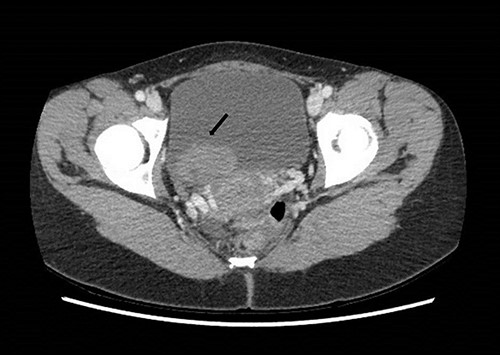

The patient received a bladder washout and continued on continuous bladder irrigation. She was afebrile and normotensive. Laboratory findings showed raised creatinine at 140 mmol/L, Hb was 13 gm/dL with subsequent drop to 9 gm/dL during the admission. Urine culture didn’t show signs of infection. Computed Tomography (CT) abdomen and pelvis with contrast demonstrated a solid mass in the bladder and a hypodense filling defect extending from the left renal pelvis to the proximal ureter with hydronephrosis (Figs 1 and 2).

Computed tomography on presentation showing a bladder mass (arrow).

Computed tomography on presentation showing the hypodense filling defect extending from the left renal pelvis to the proximal ureter with associated hydronephrosis (arrow).